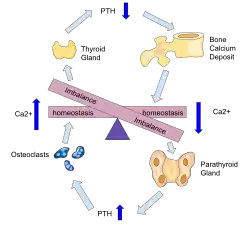

Parathyroid hormone is responsible for the induction of increased calcium absorption in the gastrointestinal tract or gut and in the kidney. It also induces calcium and phosphate resorption from the bone by osteoclasts.[15][11] Parathyroid hormone also plays a role in activating vitamin D from its pro form to its active form.[15] Vitamin D is also responsible for increased blood calcium levels and works in conjunction with parathyroid hormone. Vitamin D is also partly responsible for the inhibition of parathyroid hormone release by binding Vitamin D receptors at the parathyroid gland.[11]

During prolonged secondary hyperparathyroidism increased blood phosphate levels drive hyperplasia of the parathyroid gland and this acts to reset calcium sensitivity at the calcium sensing receptors leading to tertiary hyperparathyroidism after resolution of the secondary form with the continued release of parathyroid hormone in the presence of hypercalcemia.[11]